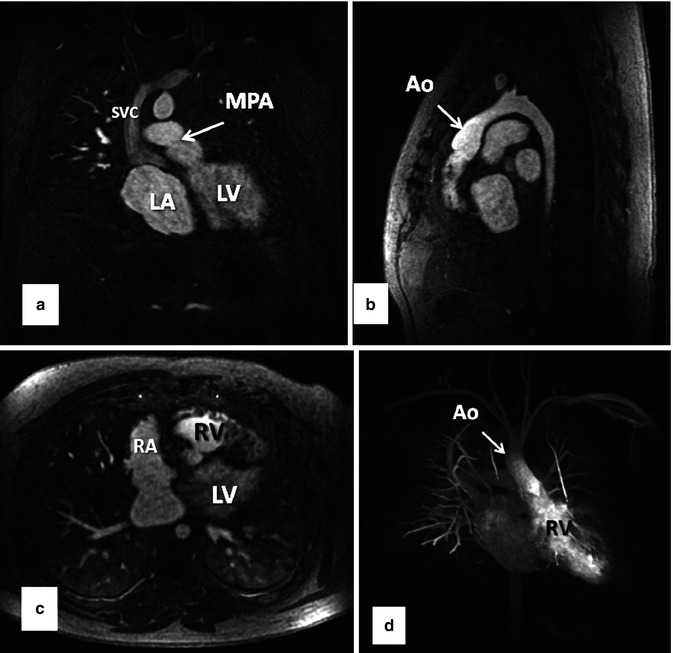

From radiologykey.com

ContrastEnhanced Resonance Angiography Radiology Key Def Magnetic Resonance Angiography A magnetic resonance angiogram (mra) is a noninvasive test that allows your provider to see your blood vessels and blood. Magnetic resonance angiography (mra) is a technique which is used to evaluate and study the blood vessels and identify any abnormalities. Magnetic resonance angiography (mra) encompasses several imaging techniques based on magnetic resonance imaging (mri) developed for studying the. Magnetic. Def Magnetic Resonance Angiography.

(a to d). Resonance Angiography (MRA) showing (a) Aneurysmal Def Magnetic Resonance Angiography Magnetic resonance angiography (usually shortened to mr angiography or mra) is an alternative to conventional angiography and. Magnetic resonance angiography (mra) is a technique which is used to evaluate and study the blood vessels and identify any abnormalities. Magnetic resonance angiography (mra) encompasses several imaging techniques based on magnetic resonance imaging (mri) developed for studying the. In magnetic resonance angiography. Def Magnetic Resonance Angiography.